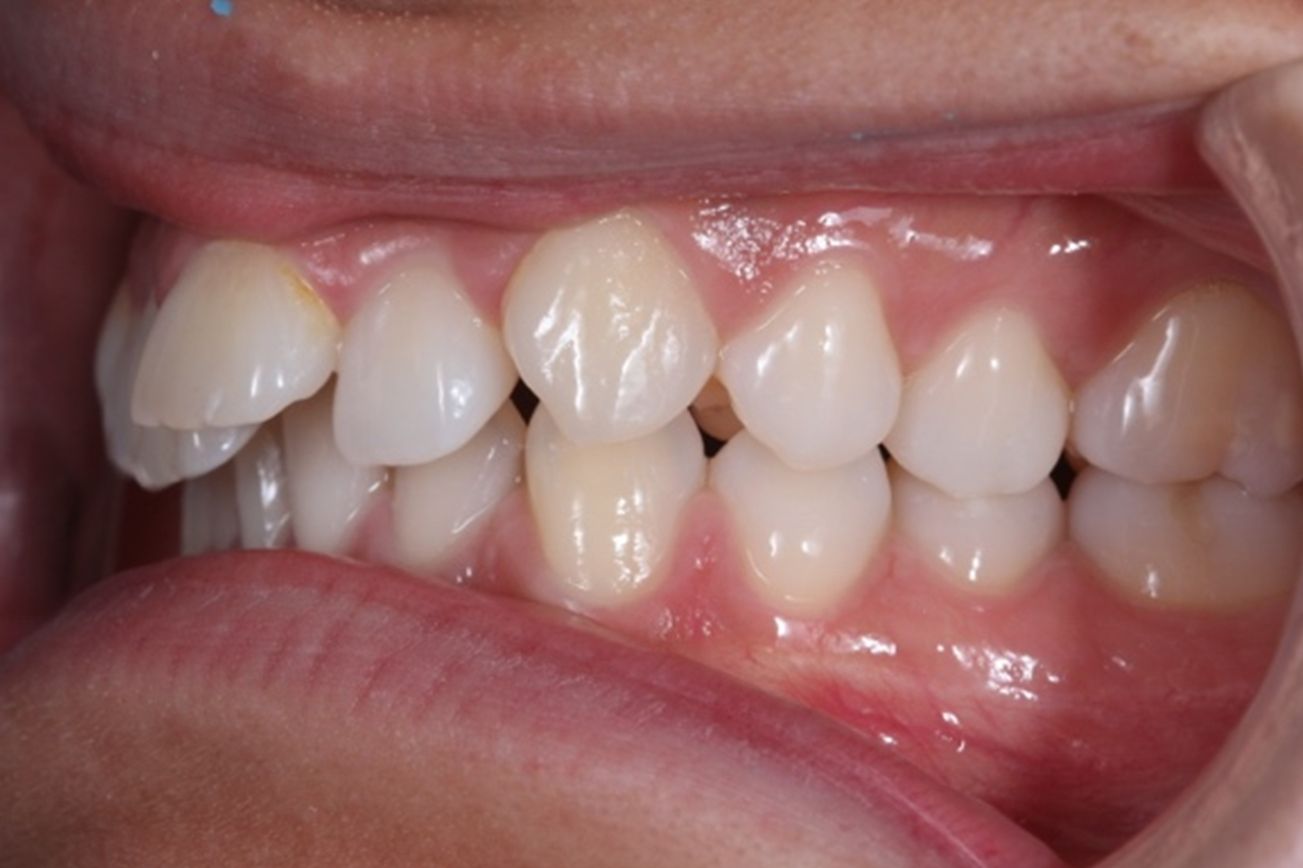

A continuación, mostramos el caso de una paciente adulta con clase II ósea y dentaria.

Con Ortodoncia Invisible, y gracias a la cooperación de la paciente, conseguimos este resultado y, lo más importante de todo, que la paciente sonría sin complejos.